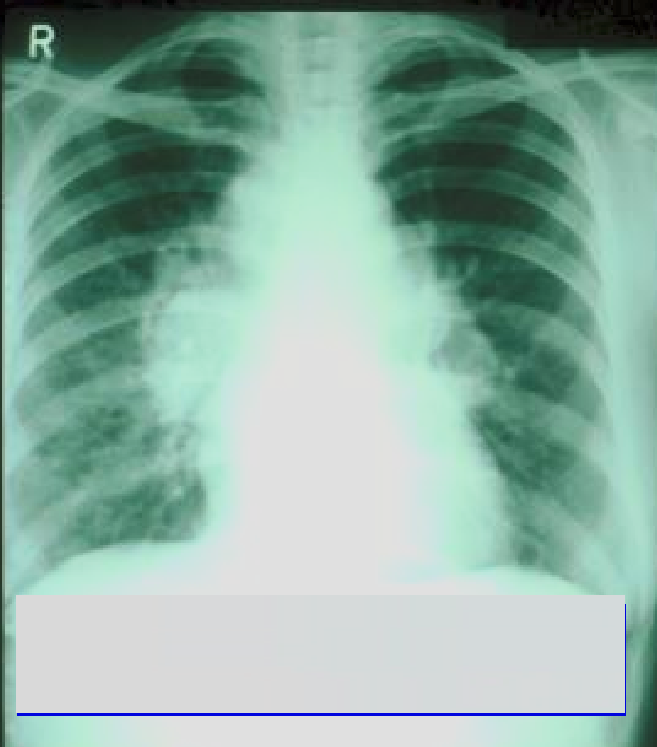

30

What diseases can asbestos cause ?

Pleural disease 1) Benign pleural plaques - asymptomatic 2) Acute asbestos pleuritis - fever, pain, bloody pleural effusion 3) Pleural Effusion and Diffuse pleural thickening - restrictive impairment 4) Malignant Mesothelioma - incurable pleural cancer. Presents with chest pain and pleural effusion. No available treatment - fatal within two years. (diaphragmatc calcifications = think absestos, calcified plaque same colour as bone) Pulmonary Fibrosis - “Asbestosis” -Diffuse pulmonary fibrosis and restrictive defect due to heavy prolonged exposure. -Asbestos bodies in sputum. -Asbestos fibres in lung biopsy. Bronchial carcinoma - asbestos multiplies risk in smokers | Abestosis should mean pulmonary fibrosis due to asbestos